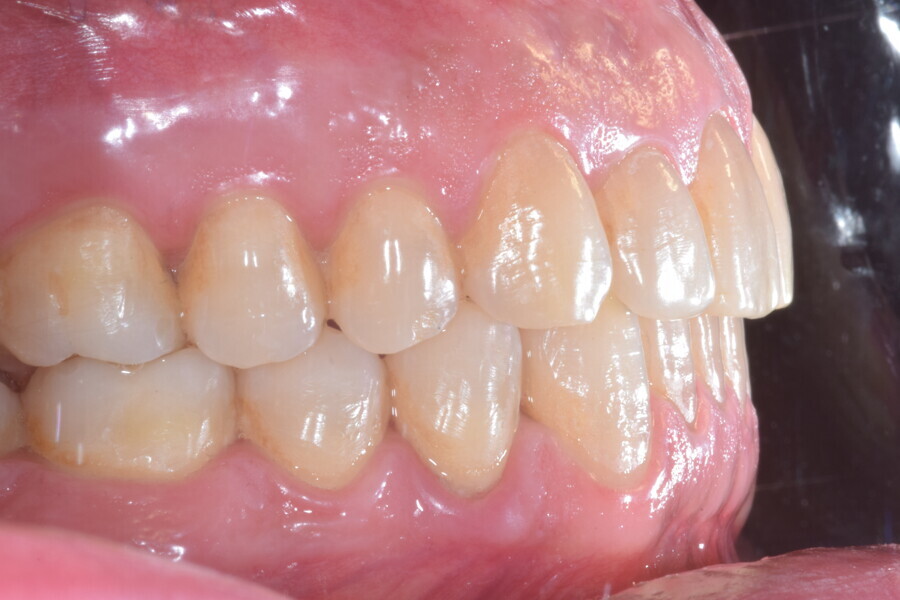

A 37-year-old male patient presented with the chief need for re establishing anterior alignment in both arches. Facial analysis showed a short face with a flat profile but proper chin projection (Figs. 9–12), and clinical examination revealed a skeletal Class I (ANB = 0.89°) and dental Class I malocclusion with severe deep bite (almost 100%), a deep curve of Spee, normal maxillary central incisor torque (Ui–FH = 110°), mild maxillary crowding and moderate mandibular crowding (Figs. 13–18). The deep bite components were represented in this patient by the severe skeletal condition of hypo divergent pattern (FMA = 14.24°) with normal maxillary and mandibular incisor inclination and decreased gonial angle (110.46°). Analysis of the cephalometric radiograph indicated a reduced lower anterior facial height, combined with a hypo-divergent pattern (Fig. 19). The only treatment option suggested was orthodontic treatment with aligners for deep bite correction with all the features described (bite ramps, pressure area, 3D curve of Spee levelling, Class II elastics and heavy occlusal contacts).

Fig. 13

Fig. 14

Fig. 15

Fig. 16

Fig. 17

Fig. 18